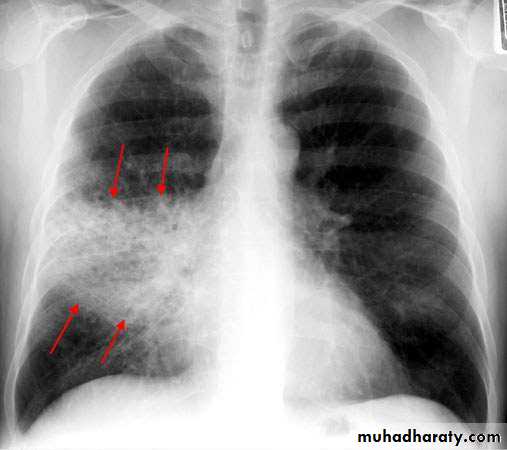

Bronchopneumonia

• Typically patchy and segmental shadowing

Complications

Staph. aureus

• multilobar shadowing, cavitation, pneumatocoeles and abscesses.

• BRONCHOPNEUMONIA

• Centrilobular and Peribronchiolar opacity pneumonia• Tends to be multifocal

• Patchy in distribution rather than localized to any

• one lung region